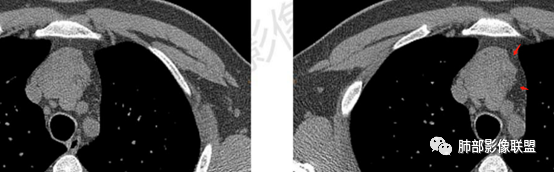

南边分析-征象标注

2、下半部分,形态自然,边缘稍膨隆,内部密度实性夹杂稍低密度影,而且是线样低密度影,比较自然走形,支持胸腺组织增生或残留。如果其他肿瘤所致,应该是边缘膨隆,类圆形,内部密度均匀,或部分区域坏死,或者结节状灶之间间隔。所以这个首先:胸腺增生或残留应该有。

* 部分区域边缘平直、稍凹陷,部分密度较低,边缘稍膨隆。

* 部分密实。因为没有增强,附近血管分不开,内部密度差不是那么明显,但是有密度差。提示:内部组织结构有变化,不是单一的组织结构。

Chairman:这个其实还是对MR化学位移相位的理解问题。同反相位测出的是“水脂混合”信号,只要脂肪与水混合的足够好,反相位下都是信号减低。这也是脏器边缘在反相位下呈“勾边效应”的原理。脏器包膜里面有脂肪,腹腔内有水,所以在水脂交界处会形成反相位下的“黑线”。我借用一下下面这个图:胸腺里面CT平扫密度低,水脂混合成分。放大了看能发现里面分散分布的微小脂肪颗粒反相位信号应该可以看到减低。也就是说,反相位的信号减低可以是脂肪变性,也可以是微小的脂肪与水分混合~乳浊液。本质上都是“水脂混合成分”。

2、前纵隔梨形软组织密度影,与正常胸腺形态一致,为胸腺弥漫性增大,两缘匀称,质地柔软,未见明显膨隆,其内可见脂肪浸润影,与周围结构分界清楚,再加上病人年龄,需要高度提示胸腺增生(淋巴滤泡样增生型)。胸腺瘤一般无脂肪浸润,质地较硬,呈结节或肿块状,且发病年龄较大。B2B3型肿块边界不清,可侵犯临近组织脏器,B3可胸膜转移,胸腺癌可引起纵隔淋巴结及远处转移。